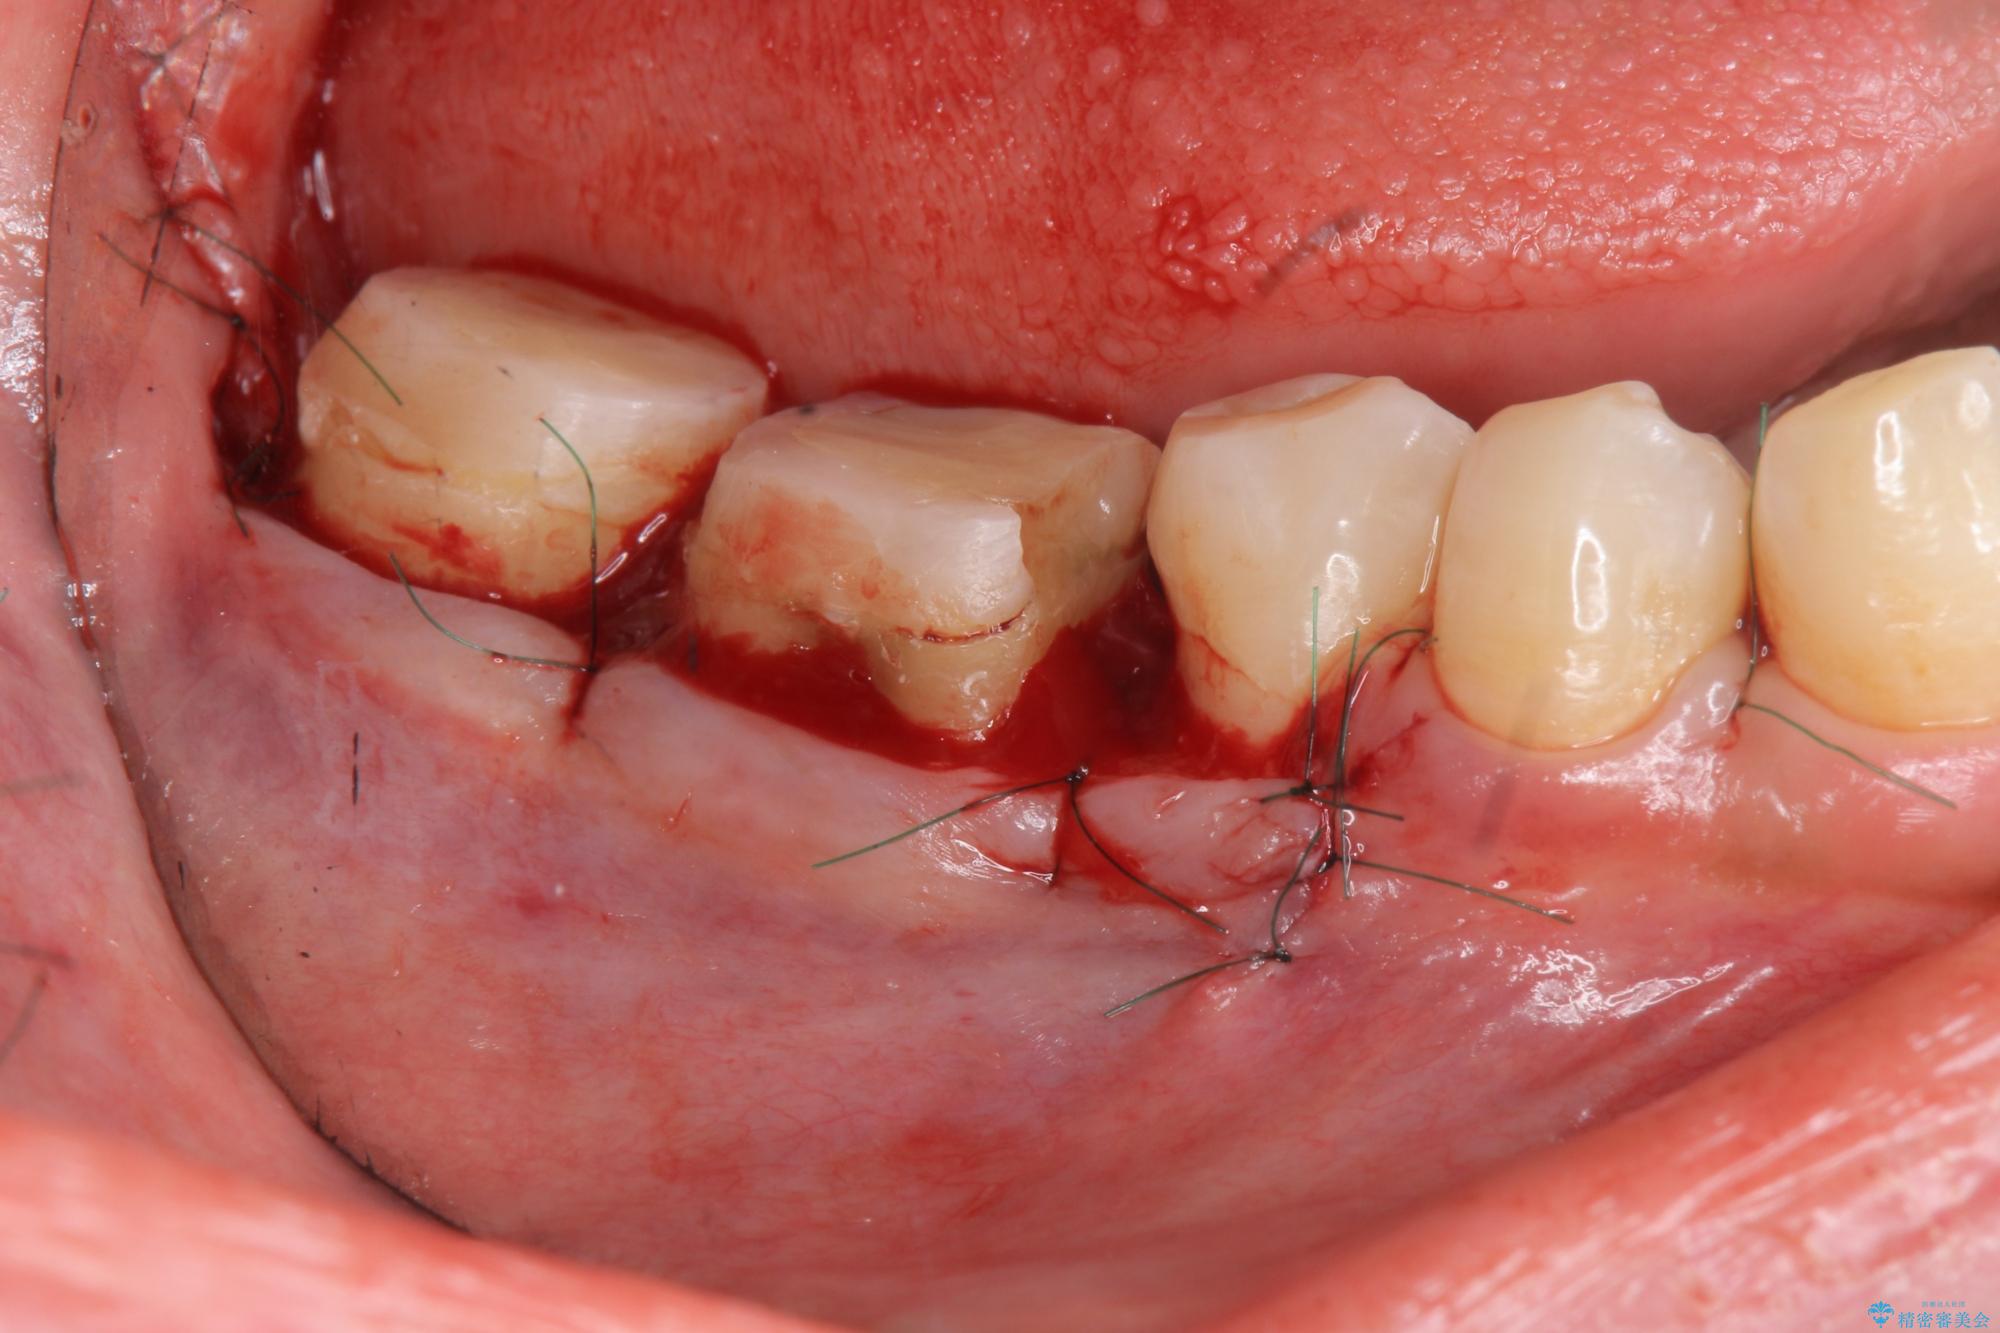

歯周外科を行うことで、歯ぐきの位置を下げ歯の高さを作り出し安定したクラウンの装着が可能となります。また同時に舌の邪魔となっていた骨隆起の除去を行うこととしました。

歯周外科に際しては、静脈内麻酔を行うことでほとんど記憶のないうちにリラックスした状態で受けていただくことができました。